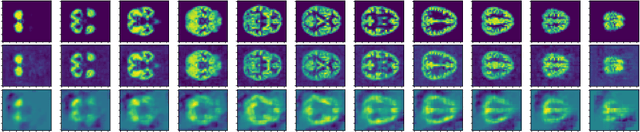

Abstract:Recently, there has been growing interest in the analysis of spectrograms of ElectroEncephaloGram (EEG), particularly to study the neural correlates of (un)-consciousness during General Anesthesia (GA). Indeed, it has been shown that order three tensors (channels x frequencies x times) are a natural and useful representation of these signals. However this encoding entails significant difficulties, especially for convolutional sparse coding (CSC) as existing methods do not take advantage of the particularities of tensor representation, such as rank structures, and are vulnerable to the high level of noise and perturbations that are inherent to EEG during medical acts. To address this issue, in this paper we introduce a new CSC model, named Kruskal CSC (K-CSC), that uses the Kruskal decomposition of the activation tensors to leverage the intrinsic low rank nature of these representations in order to extract relevant and interpretable encodings. Our main contribution, TC-FISTA, uses multiple tools to efficiently solve the resulting optimization problem despite the increasing complexity induced by the tensor representation. We then evaluate TC-FISTA on both synthetic dataset and real EEG recorded during GA. The results show that TC-FISTA is robust to noise and perturbations, resulting in accurate, sparse and interpretable encoding of the signals.

Abstract:This paper introduces a new multivariate convolutional sparse coding based on tensor algebra with a general model enforcing both element-wise sparsity and low-rankness of the activations tensors. By using the CP decomposition, this model achieves a significantly more efficient encoding of the multivariate signal-particularly in the high order/ dimension setting-resulting in better performance. We prove that our model is closely related to the Kruskal tensor regression problem, offering interesting theoretical guarantees to our setting. Furthermore, we provide an efficient optimization algorithm based on alternating optimization to solve this model. Finally, we evaluate our algorithm with a large range of experiments, highlighting its advantages and limitations.